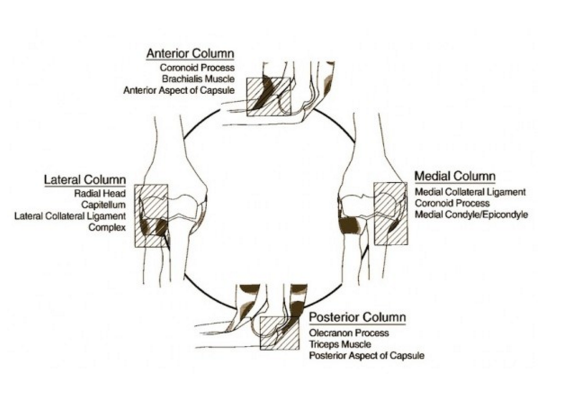

Caution can help reduce your risk of a dislocated elbow. The act of restoring alignment to the elbow is called a reduction maneuver. Types of reduction of elbow dislocation first aid immediately after the injury you should put.